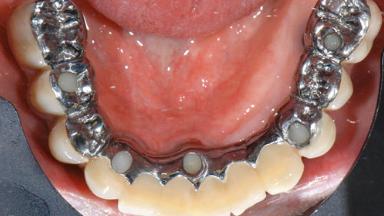

A 77-year-old male patient was referred for the management of frequent and repeated acrylic fracture of his existing mandibular fixed full-arch implant-supported metal/acrylic prosthesis. He also complained about softtissue soreness and the lack of retention and stability of his maxillary removable partial metal/acrylic prosthesis. Both prostheses had been delivered two years previously as part of his full-mouth rehabilitation (caries, tooth wear, tooth fracture). His medical history revealed high blood pressure, controlled with the use of antihypertensive medication.

# of Implants | 5 |

Prosthesis Type | FDP |

Retention | Screw-retained, with 4 or more splinted implants Screw-retained, with 4 or more splinted implants |